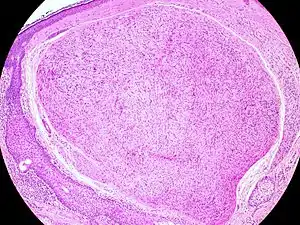

| Micrograph of a palisaded encapsulated neuroma | |

PEN is diagnosed by clinical recognition of the lesion and on subsequent histologic examination. Typically, the lesions are suspected to be schwannomas or neurofibromas clinically with PEN being an incidental finding on histology.[3]

PEN is typically diagnosed in patients between the ages of 40 and 60 years and occurs more frequently in females than males. The diagnosis of PEN may be difficult, even with confirmatory histology, due to its histological similarities with schwannomas and neurofibromas. It is imperative that the correct diagnosis is made the misdiagnosis of a neurofibroma may lead to unnecessary further investigation into associated systemic syndromes such as neurofibromatosis type 1 or multiple endocrine neoplasia syndrome.[3][4]